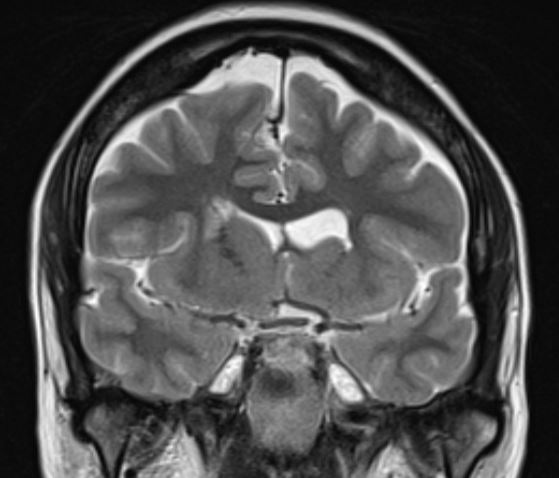

The structural correlates of the above EEG findings appear below. There is enlargement of the left-ventricular system, atrophy of the head, body and tail of the caudate nucleus and the left hemisphere appears modestly smaller in size than the right, most evident on axial sequences. The MRI was done while the patient was quite restless. As you can see from these pictures, the left occipital cortex and the left thalamus do not demonstrate any structural correlate to the asymmetry of alpha rhythms. However, we know from the EEG that the left hemisphere is markedly dysfunctional. Unsurprisingly, on functional MRI scans language is represented in the right hemisphere.